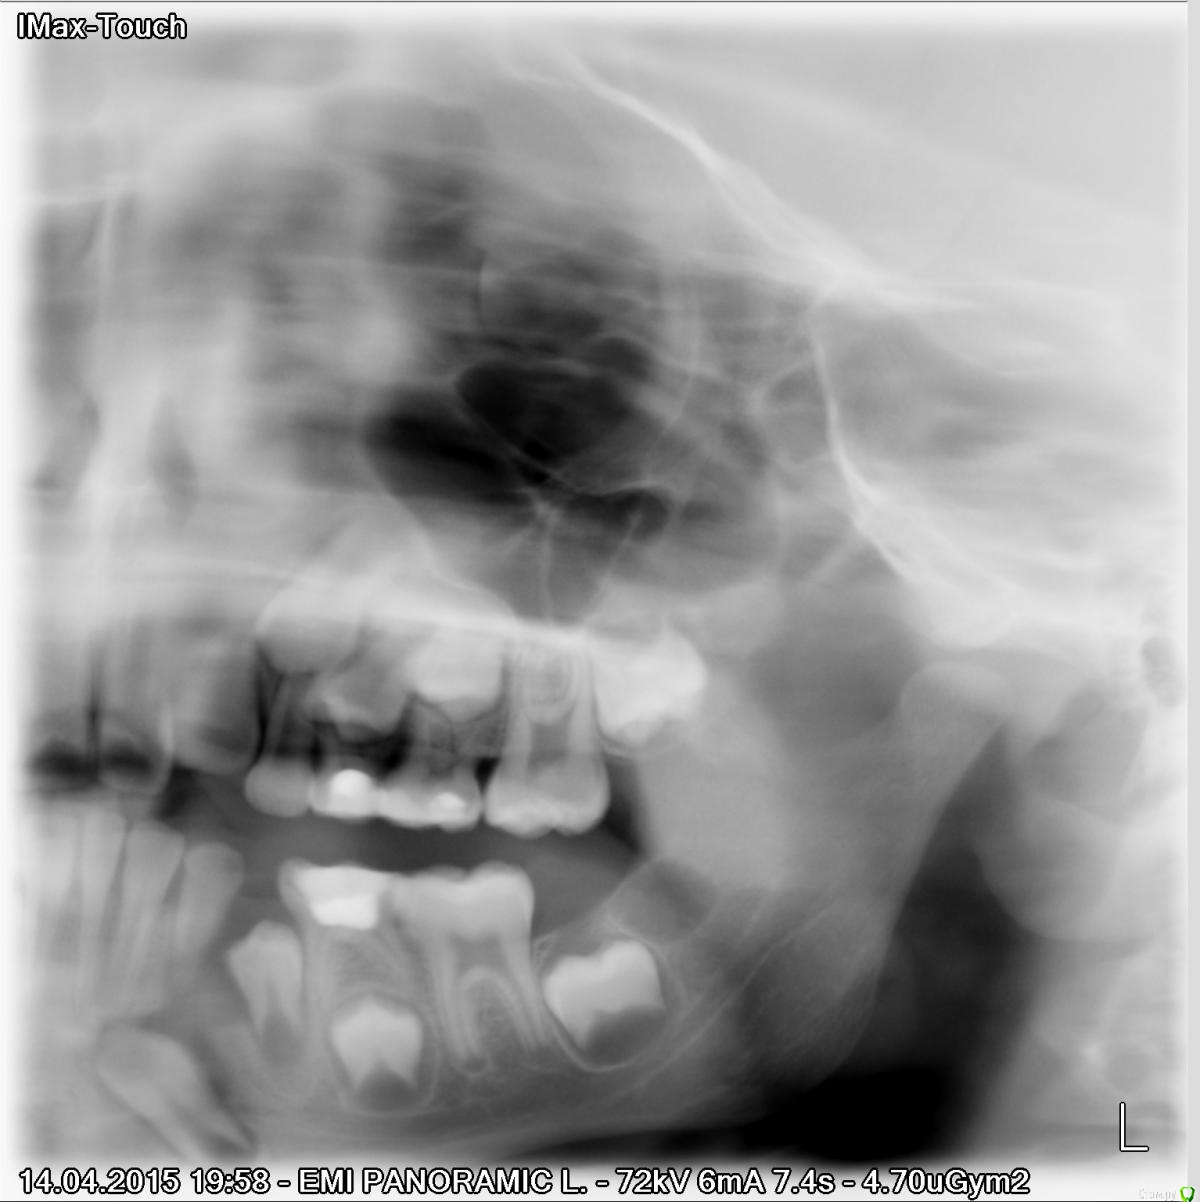

Ловягина Ксения Опубликовано 24 апреля, 2015 Автор Поделиться Опубликовано 24 апреля, 2015 Если бы выложили бы снимок, было бы проще оценивать Вот такое чудо, при внимательном рассмотрении зачатки "задеты", в ночь киста "вытекла", выбухание исчезло Ссылка на комментарий

Yana guapa Опубликовано 27 апреля, 2015 Поделиться Опубликовано 27 апреля, 2015 Они там были, с осени их лечить начнут, не знаю почему не сейчас?(((спасибо за ответполноценный снимок не хотите сделать? ОПТГ хотя бы, он и ортодонту пригодится, а в идеале еще и -КТ данной области. если жалоб нет, то ортодонтическое лечение можно было бы и начать сейчас, так как у ребенка и 7.4 рано ушел. Ссылка на комментарий

Ловягина Ксения Опубликовано 27 апреля, 2015 Автор Поделиться Опубликовано 27 апреля, 2015 полноценный снимок не хотите сделать? ОПТГ хотя бы, он и ортодонту пригодится, а в идеале еще и -КТ данной области. если жалоб нет, то ортодонтическое лечение можно было бы и начать сейчас, так как у ребенка и 7.4 рано ушел.ОПТГ есть у ортодонта, мне пришлось делать,т.к у нас он не открылся, а у меня еще "вторая половинка" есть, ассистент ошиблась 1 Ссылка на комментарий